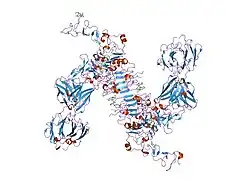

The ErbB family consists of four individual plasma membrane-bound receptor tyrosine kinases. One of which is erbB-2, and the other members being erbB-1, erbB-3 (neuregulin-binding; lacks kinase domain), and erbB-4. All four contain an extracellular ligand binding domain, a transmembrane domain, and an intracellular domain that can interact with a multitude of signaling molecules and exhibit both ligand-dependent and ligand-independent activity. Notably, no ligands for HER2 have yet been identified.[13][14] HER2 can heterodimerise with any of the other three receptors and is considered to be the preferred dimerisation partner of the other ErbB receptors.[15]

Dimerisation results in the autophosphorylation of tyrosine residues within the cytoplasmic domain of the receptors and initiates a variety of signaling pathways.

An important downstream effect of trastuzumab binding to HER2 is an increase in p27, a protein that halts cell proliferation.[35] Another monoclonal antibody, Pertuzumab, which inhibits dimerisation of HER2 and HER3 receptors, was approved by the FDA for use in combination with trastuzumab in June 2012.